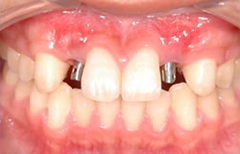

自己採血してCGF&AFGを再生に使用した症例

<治療前>

上顎前歯部が崩壊して残すことが出来ない状態になっている。

<治療後>

抜歯した部位にインプラントを埋入し半年かけて

歯肉と歯槽骨を再生させて審美的な歯(セラミック冠)を入れました。

抜歯即時インプラント症例

抜歯をして即にインプラント埋入を行う治療